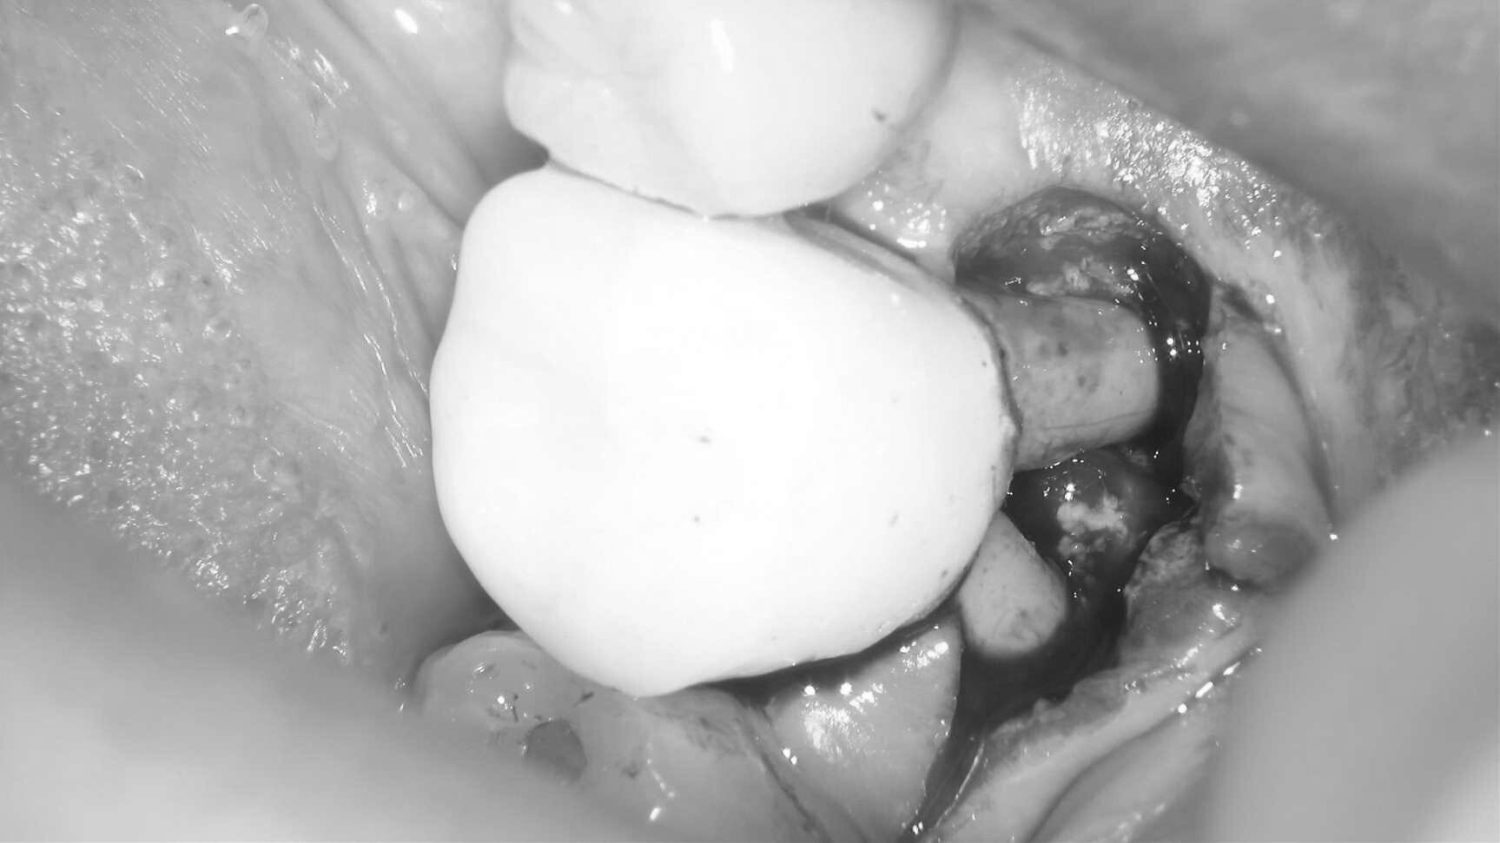

| 主訴 | 歯が折れたため来院。 |

| 治療内容 | 抜歯とともにソケットプリザベーション(歯槽骨再生療法)を行い、歯槽骨の再生を行う。その後にインプラントの埋入処置を行いました。 |

| 治療費 | ソケットプリザベーション:55,000円(税込、オプション別) オプション(エムドゲイン+ベリプラスト):49,500円(税込) インプラント埋入処置:418,000円(税込、埋入~上部構造含め) |

| 治療期間 | 9ヶ月 |

| 治療回数 | 10回 |

| 想定されたリスク | 再生療法を行っても、骨に置換されない場合もあり、その場合は追加的な処置もしくはインプラント埋入自体を断念しなければならない可能性もありました。 |